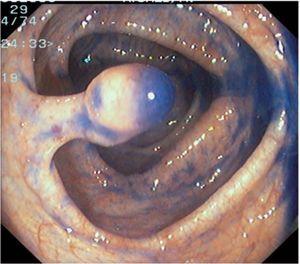

Fig. 3. Examples of flat lesions with conventional examination and after the application of indigo carmine 0.2-0.5%. a, b) Small flat adenoma, 3 mm in size. c, d) Large flat adenoma, 15 mm in size. e, f) Completely flat lesion (IIb in the Japanese classification). g, h) Depressed lesion, 3 mm in size) (IIc in the Japanese classification). I, J) Depressed lesion, 7 mm in size, histopathological study revealed submucosally invasive cancer (traditionally IIc in the Japanese classification, although recently such depressed lesions with a distinct central protrusion indicating submucosal invasion are termed IIc + Is). k, l) Flat elevated lesion with central depression, 10 mm in size, corresponding to a submucosally invasive cancer (IIa + IIc in the Japanese classification).